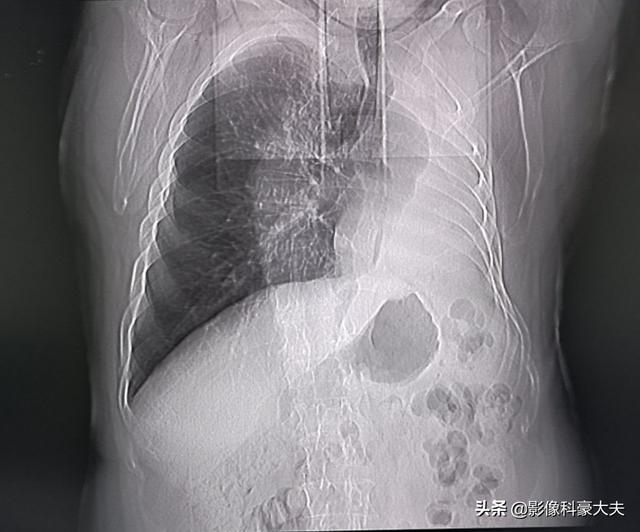

肺葉下切除(分葉切除や楔状切除)は、切除される肺組織が少なく、正常な肺組織が多く残るため、肺機能への影響が少ない。肺組織がより多く切除されるため肺葉切除術が行われた場合、正常な肺組織が相対的に少なくなり、肺機能への影響が大きく、胸部不快感を引き起こしやすくなります。次の写真は2種類の肺切除の肺を示しています。 上の写真は右下肺結節肺葉切除術で、術後右肺がかなり小さくなっているのがわかります。下の写真は左下肺結節の肺葉下切除術で、術後左肺が大きくなっているのがわかります。